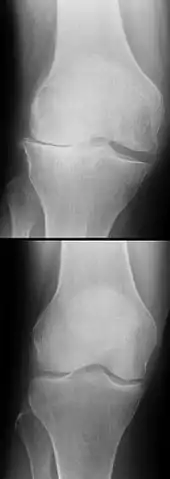

Les ruptures de LC apparaissent la plupart du temps sans cause extérieure, mais par un changement soudain de direction pendant la course ou le saut. Ce sont les blessures les plus courantes cliniquement concernant l'articulation du genou. La rupture des LC peut être diagnostiquée par une étude des symptômes (tiroir antérieur ou extérieur) lors d'un examen clinique et par la description des conditions de survenue de la déchirure. Ce diagnostic peut être confirmé par IRM et arthroscopie. Les ruptures de LC non soignées peuvent conduire à d'importants dommages dégénératifs du genou. Le traitement peut être d'ordre conservatoire ou chirurgical (microchirurgical par arthroscopie). Le choix du traitement, sa date et la méthode à utiliser, font encore l'objet de discussions très controversées. Il est par contre reconnu généralement qu'aucun traitement ne peut actuellement rétablir l'état d'un LC sain. Les suites à long terme d'une rupture de LC comprennent un risque augmenté de formation d'arthrose du genou, indépendamment du traitement effectué.

La perte du LCA perturbe la fonction d'un des deux éléments passifs centraux de guidage (stabilisateurs primaires[9]) du genou. Il en résulte une liberté de mouvement pathologique de la tête du tibia vers l'avant (ventrale), ce que l'on appelle « glissement vers l'avant du tibia ». La capsule articulaire, les ligaments latéraux, le LCP et les ménisques sont sollicités en excès pour freiner ce glissement vers l'avant du tibia. Ceci aboutit à une surextension des structures ligamentaires. Un accroissement de ce glissement aboutit à des lésions des cartilages. Celles-ci sont entre autres conditionnées par la surcharge du cartilage. Une surcharge additionnelle conduit dans ce cas à une usure prématurée, et à une arthrose. Les lésions des ménisques et du cartilage accompagnant une rupture du LCA favorisent le risque d'arthrose[10].

L'instabilité due à une rupture de LC a comme conséquence la surcharge du cartilage et des ménisques interne et externe. Quand l'instabilité n'est pas compensée par la musculature ou éliminée par une opération, il arrive souvent une rupture de ménisque et/ou une usure du cartilage accompagnée d'arthrose.